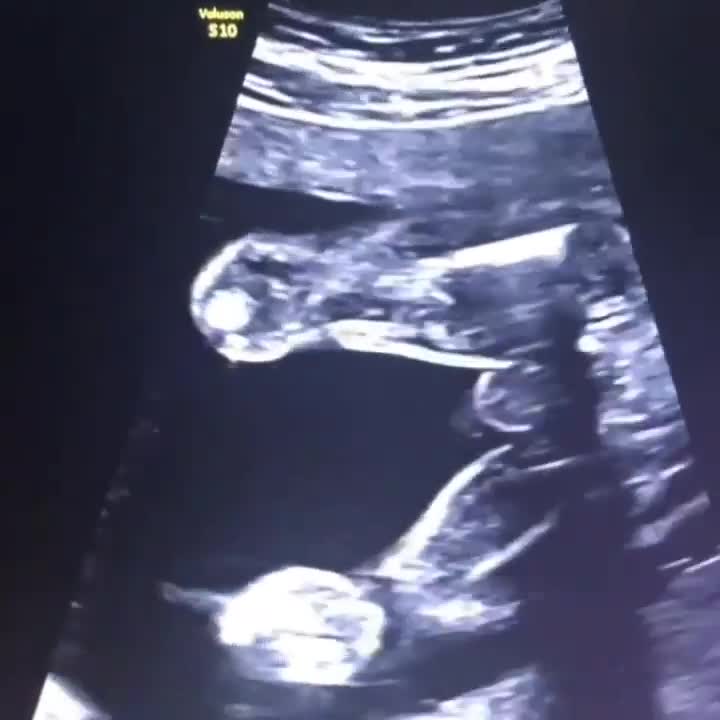

. این فیلم( سونوگرافی) نشان دهنده ی ادرار کردن جنین پسر و تشکیل مایع #آمنیوتیک یا همان آب دور بچه است. #مایع_آمنیوتیک (AF) برای رشد و نمو طبیعی جنین بسیار مهم است. ● در نیمه دوم بارداری ، این مایع توسط ادرار و مایع ریه جنین تولید می شود و با بلعیدن جنین جذب می شود پس ترکیب #AF (مایع آمنیوتیک یا در اصطلاح آب دور بچه) منعکس کننده ترکیبی از مایع ریه جنین و ادرار جنین است. حجم روزانه ادرار  دفع شده ی جنین تقریباً ۳۰ درصد از وزن بدن جنین است . 🛑استراحت مادر در موقعیت خوابیده به پهلوی سمت چپ به طور قابل توجهی تولید ادرار جنین را افزایش می دهد . تولید ادرار جنین در 14 روز قبل از زایمان کاهش می یابد. 🛑سرعت تولید ادرار جنین با شرایط مرتبط با نارسایی جفت کاهش می یابد (به عنوان مثال ، پره اکلامپسی یا همان مسمومیت بارداری ، محدودیت رشد جنین)و با شرایط مرتبط با نارسایی قلبی افزایش می یابد (به عنوان مثال ، کم خونی جنین ، تاکی کاردی فوق بطنی جنین ).